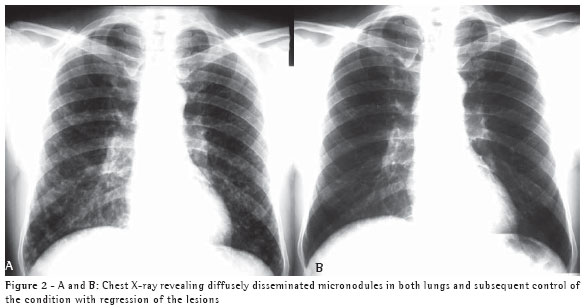

A 50-year-old white male, resident of the city of Blumenau and a stonemason, presented a clinical profile similar and simultaneous to that described in Case 1 ten days after the cleaning of the same area, in which there was bat guano. The patient was exposed to a large quantity of dust in an enclosed space. The patient was hospitalized for seven days. Two chest X-rays, one presenting diffusely disseminated micronodules in both lungs and one showing the subsequent control of the condition, are shown in Figures 2A and 2B.

Epidemiological history can raise diagnostic suspicion. Knowledge of clinical syndromes, together with clinical suspicion, can avoid the use of empirical treatment. Radiological findings, negative test results, and the high frequency of tuberculosis in Brazil were the motivations for prescribing tuberculosis treatment for both patients. Immunodiffusion test results, although negative for these two patients, have high sensitivity and are positive in approximately 75% of cases.(6) Length of exposure determines disease severity. This explains the fact that the second patient, who was the one who swept the area, presented a more severe form of the disease, with diffuse pulmonary alterations on the chest X-ray, and required hospitalization. However, a short exposure time results in focal pulmonary lesions, as in Case 1.